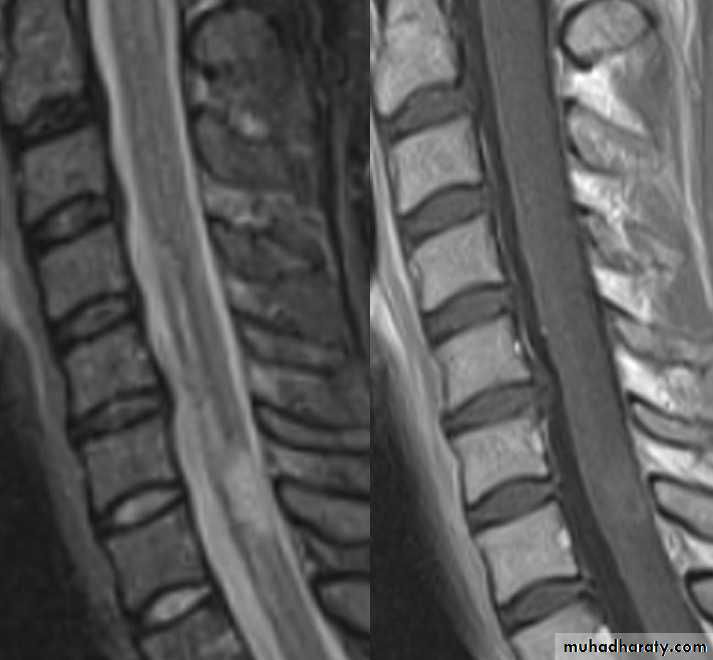

MRI FINDINGS

Patchy areas of white matter in paraventricular cerebral areasLesions in cerebellum/brainstem/ cervical and thoracic spinal cord

Gadolinium enhancement identifies active lesions